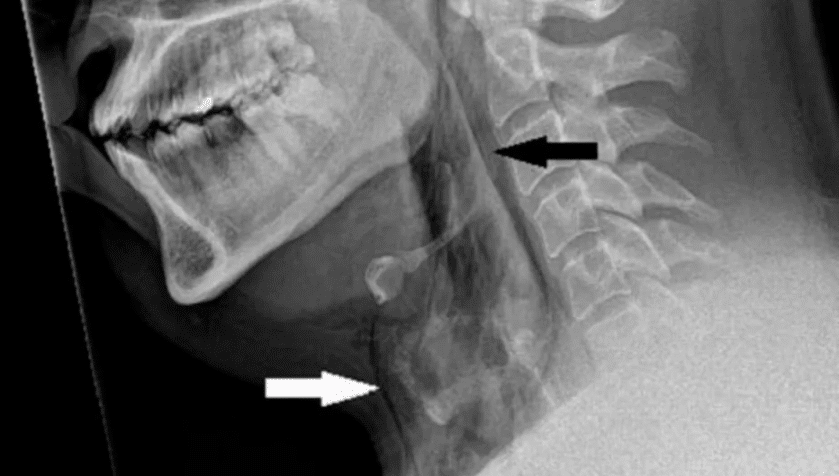

El hombre, quien tenía antecedentes de rinitis alérgica, experimentó una inflamación inmediata en el cuello, por lo que tuvo que realizarse una radiografía, la cual permitió a los médicos de la Universidad de Dundee diagnosticar su desgarre en la tráquea.

La herida en la tráquea del paciente tiene dimensiones de 2 milímetros x 2 mm x 5mm y se encuentra entre la tercera y cuarta vértebra. Sin embargo, tras el descubrimiento de su lesión, este permaneció en observación durante 48 horas sin que fuera necesaria ninguna intervención quirúrgica para curarlo